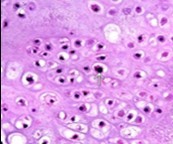

Figure 4.Enchondroma depicting lobules of hyaline cartilage with vacuolated cells and eccentric nuclei 12.

Figure 5.Enchondroma enunciating lobules of uniform cartilaginous cells with regular, centric nuclei and absence of mitosis 13.

Figure 6.Enchondroma exemplifying lobules of hyaline cartilage composed of enlarged, vacuolated cells with uniform nuclei. Focal calcification is absent 14

Figure 7.Enchondroma enunciating lobular hyaline cartilage with constituent vacuolated chondrocytes an uniform nuclei 15.

Figure 8.Enchondroma delineating hyaline cartilaginous cells with vacuolated cytoplasm and uniform nuclei 16.